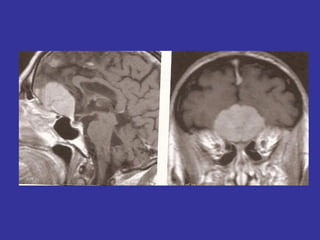

Lesões quiasmáticas (tumores de hipófise)=>

hemianopsias bitemporais

Edema de papila bilateral

– I e II pares

– tumores face inferior do lobo frontal

– atrofia óptica no lado do tumor (compressão

direta)

– edema de papila do lado oposto (HIC)

– anosmia

Síndrome de Foster Kennedy